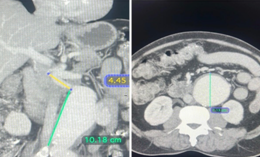

The Abdominal Aortic Aneurysm (AAA) was extending from the infra-renal aorta to both Common iliac arteries. Endovascular Aneurysm Repair (EVAR) was planned. Generally, an EVAR is done by surgically exposing femoral arteries bilaterally to take the grafts inside the aorta for Endovascular repair. We did the EVAR completely percutaneous- avoiding any surgical exposure. No Groin Cut, No surgical femoral artery exposure # SIMPLY Percutaneous. The patient Got discharged in 48 Hrs. It’s actually technically challenging to create 2 X two sets of pre-close sutures / Bilateral femoral for 20F (6mm) holes on Common femoral arteries. The procedure was done with suture closure of Bilateral 6 mm holes over the femoral without exposing the femoral - that’s the beauty.